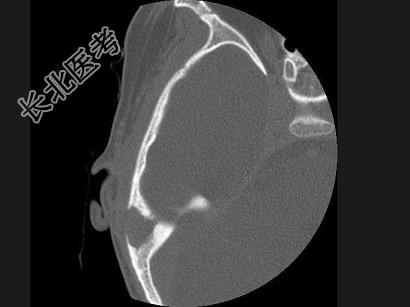

- 单项选择题女,17岁, 右耳乳突区隐痛,右耳后乳突区出现包块, 逐渐增大,CT检查如图, 最可能的诊断是 ( )

A、胆脂瘤

B、化脓性中耳炎

C、嗜酸性肉芽肿

D、中耳癌

E、听神经瘤